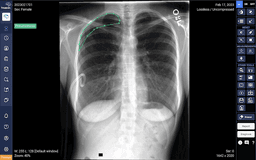

comprehensive artificial intelligence (AI) doctor assistant software developed by VinBrain

What is DrAid?